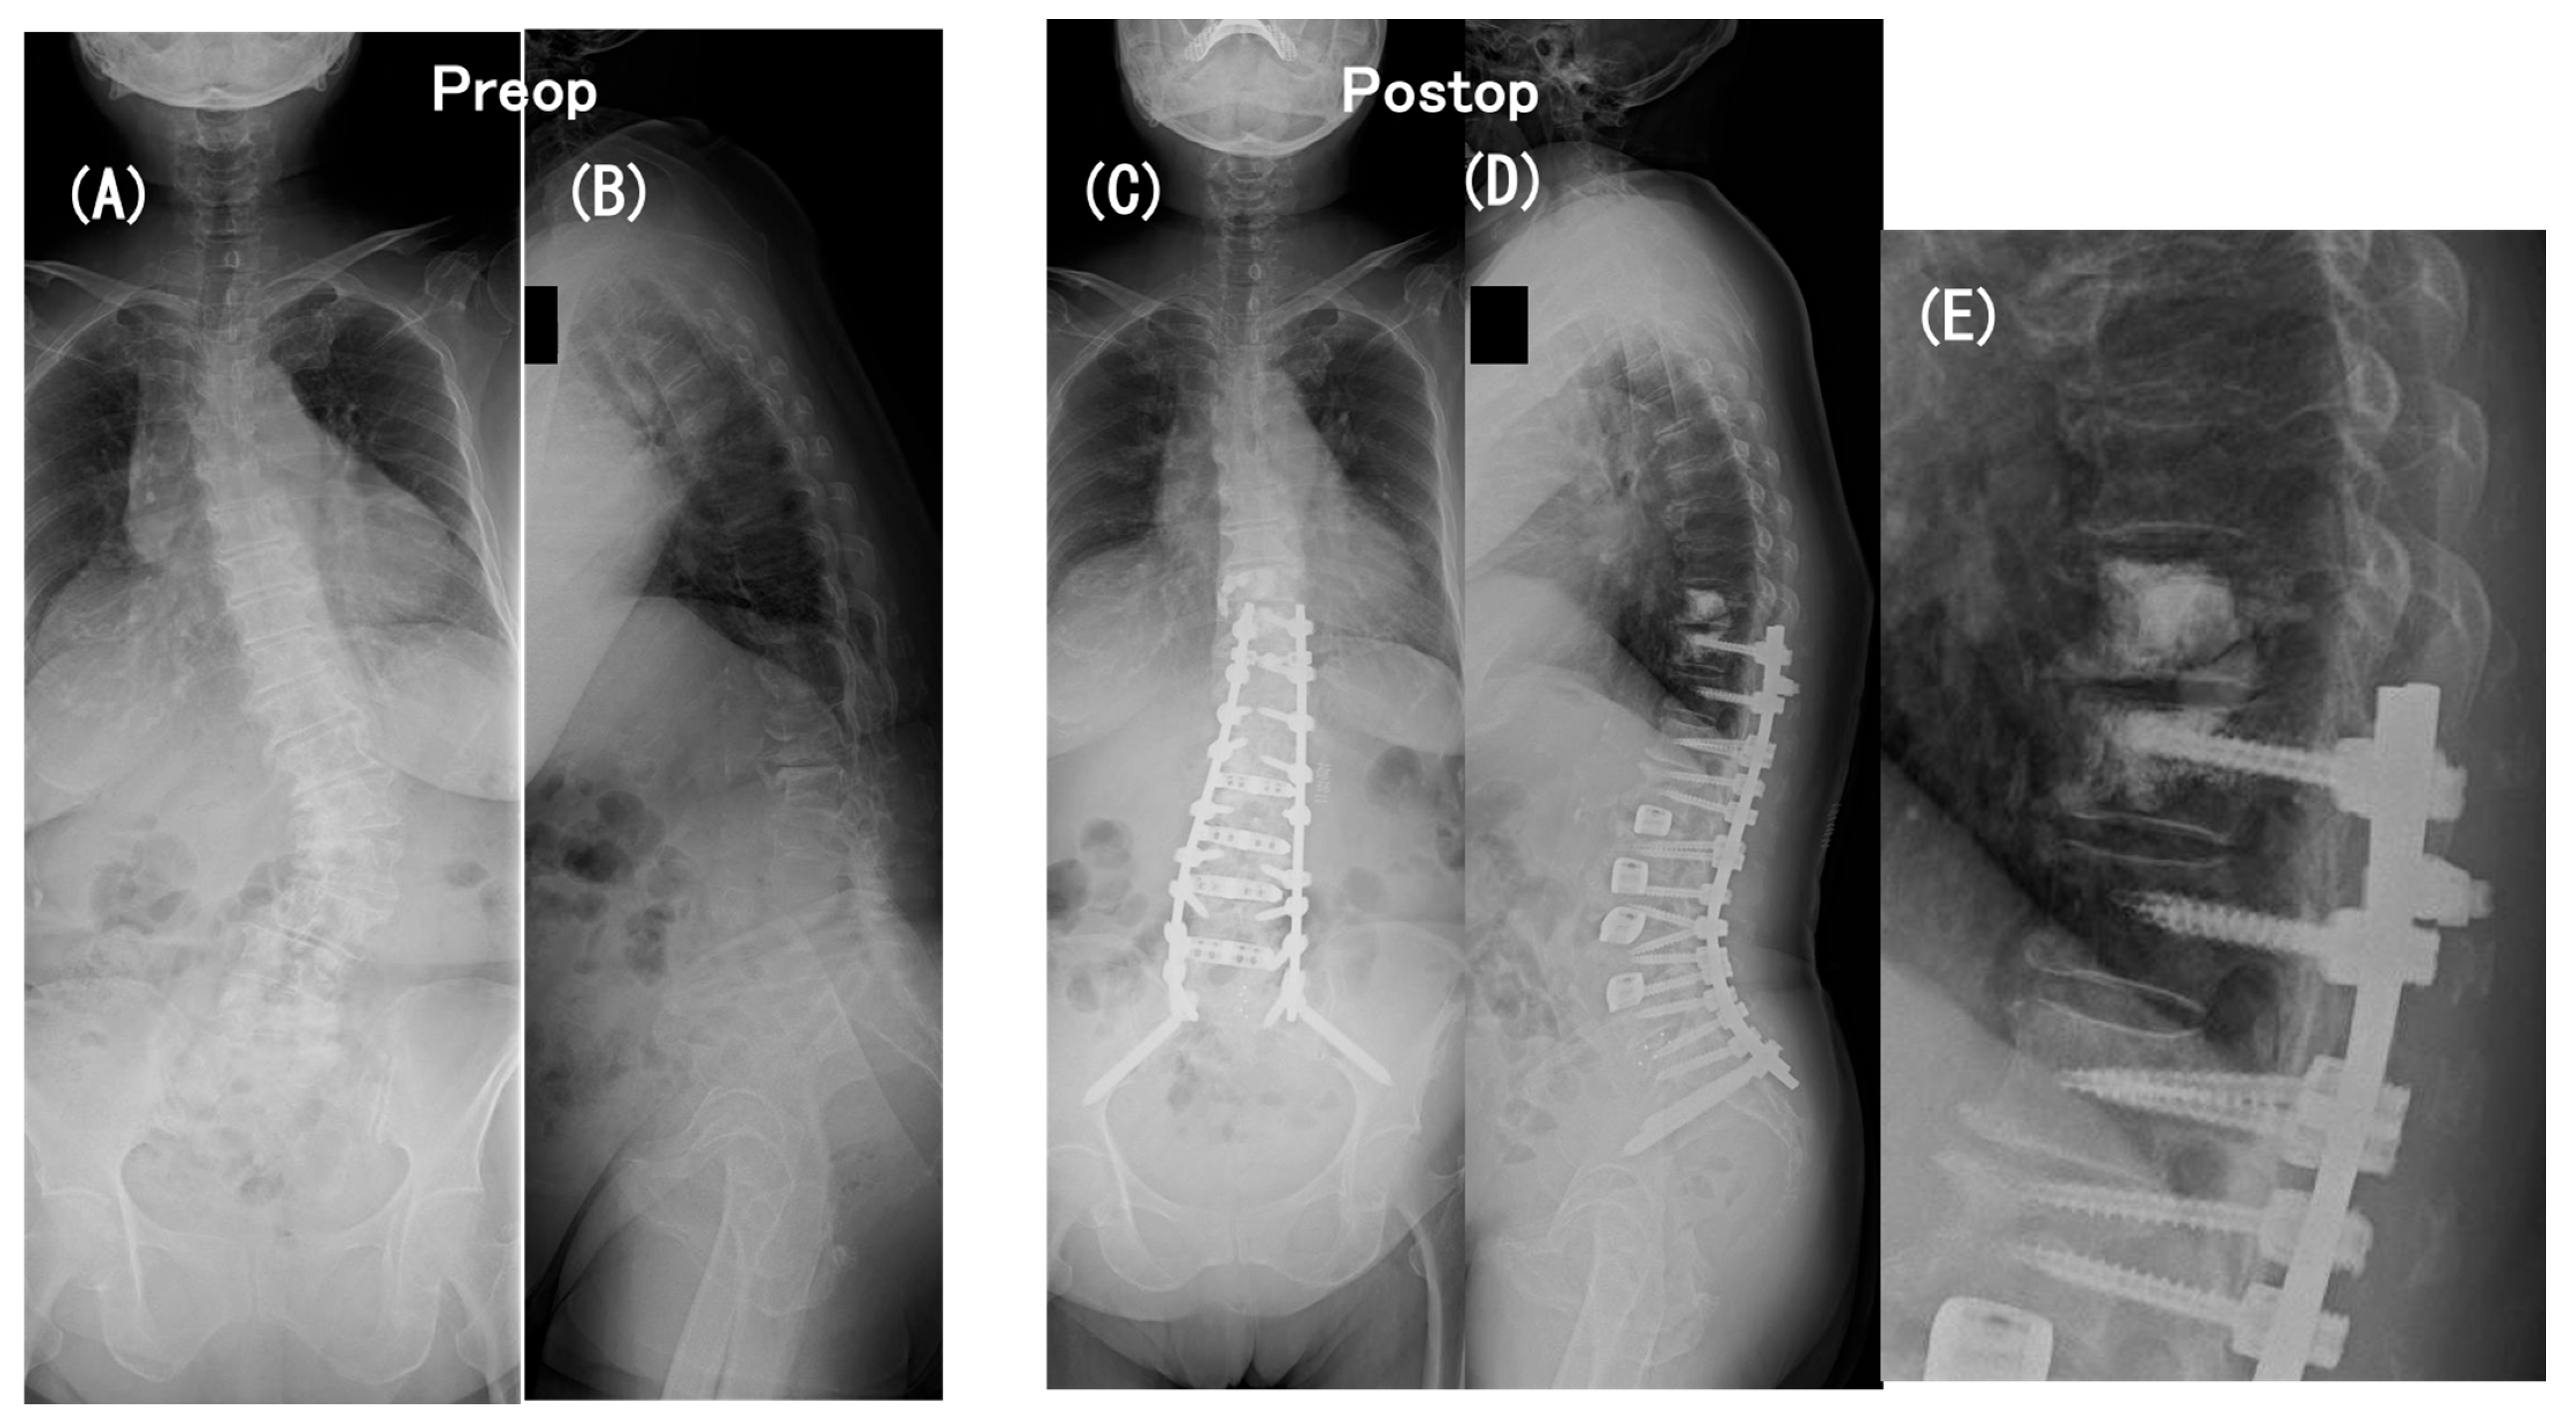

3.6. Case Presentation

- Case no. 6

- Case no. 4